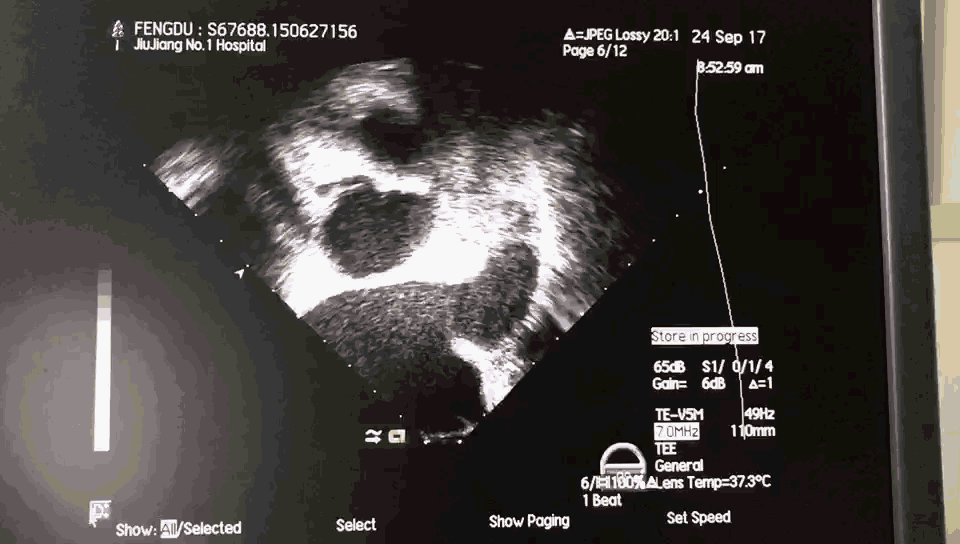

术前超声:

TEE 0:

TEE 45:

TEE 90:

TEE 135: